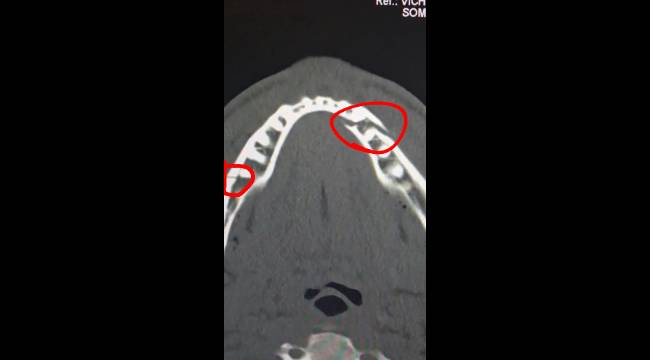

Maçın ardından fiziksel durumuyla ilgili sosyal medya platformu X (eski adıyla Twitter) üzerinden bir açıklama yapan Paul, çenesinin kırıldığını ve ameliyata alındığını duyurdu.